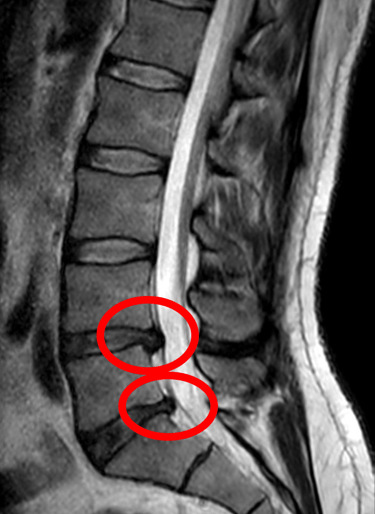

¿Qué es un Disco Herniado?

Un disco herniado ocurre cuando uno de los discos intervertebrales de tu columna se desplaza de su lugar o se rompe, presionando los nervios cercanos. Esto puede provocar dolor intenso, adormecimiento o hormigueo, especialmente en la espalda, cuello, brazos o piernas. Ya sea causado por una lesión, mala postura o el desgaste natural del envejecimiento, este problema común puede afectar significativamente tu calidad de vida.